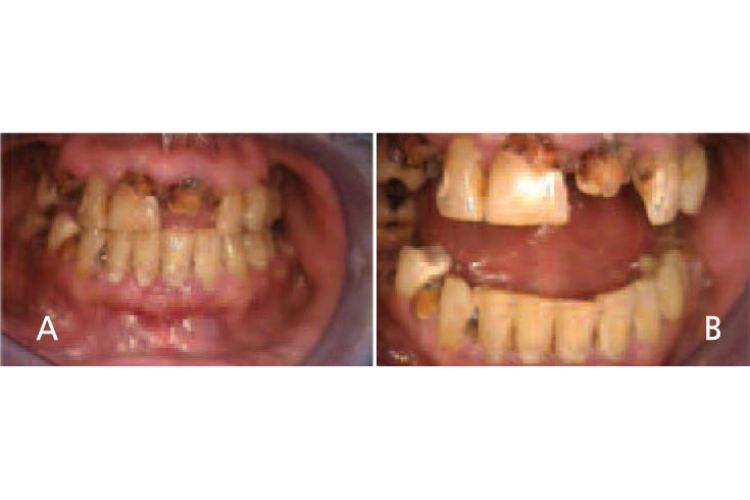

Oral manifestations in the advanced states of methamphetamine abuse include A) teeth broken off at the gingival margin; and B) grayish-brown dentition with enamel that is reduced to a soft leathery texture, along with gingivitis and acute periodontitis.